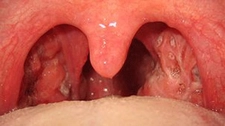

Bademcik taşları, bademciklerin üzerinde veya içinde oluşan sert, beyaz veya sarı renkteki birikintilerdir. Genellikle, bademciklerin yüzeyindeki boşluklarda (kriptalarda) biriken gıda maddeleri, ölü hücreler ve bakteri gibi maddelerin birleşiminden oluşurlar. Bu taşlar, bazı kişilerde rahatsızlık hissine, boğazda ağrıya veya kötü bir nefese yol açabilir. Bademcik taşı temizleme yöntemleri, bu taşların etkili bir şekilde çıkarılması ve tekrarlama riskinin azaltılması için önemlidir. Bademcik Taşı Nedir?Bademcik taşları, bademciklerin doğal yapısının bir sonucudur. Bademcikler, bağışıklık sisteminin bir parçası olarak görev yaparlar ve vücuda giren patojenlerle savaşmada yardımcı olurlar. Ancak, bazı durumlarda, bu taşlar birikerek çeşitli sağlık sorunlarına neden olabilir. Bademcik taşlarının oluşumunda etkili olan faktörler şunlardır: